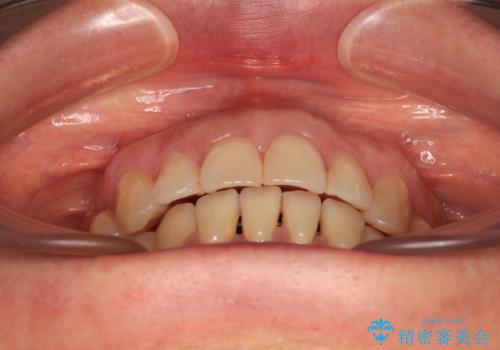

正中のズレと飛び出した前歯を改善 メタルブラケットでの抜歯矯正

- 飛び出した上顎前歯と正中のズレを気にして来院された患者様です。

上顎正中が右側にずれていたので、むし歯が酷く抜歯が必要な左側臼歯を抜歯して正中を改善することとしました。